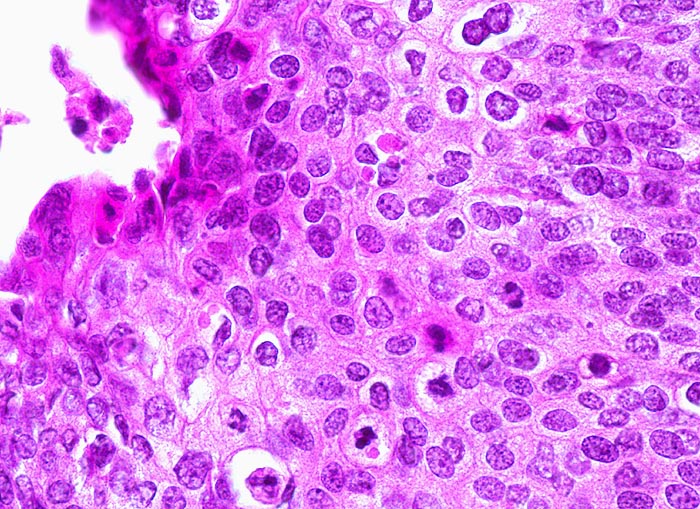

Die HPV Infektion kann gelegentlich aufgrund zytopathischer Effekte in den infizierten oberflächlichen Plattenepithelzellen erkannt werden. Die zytopathisch veränderten Zellen nennt man Koilozyten. Koilozyten weisen einen hellen perinukleären Hof und einen verdickten peripheren Zytoplasmasaum auf (> 5546) (> 5547). Sie enthalten einen oder mehrere hyperchromatische dunkle Zellkerne. Ein flaches Areal mit zytopathisch veränderten Plattenepithelzellen wird als flache kondylomatöse Läsion bezeichnet (> 1093). Die LSIL ist gekennzeichnet durch Zellatypien und Mitosefiguren im unteren Epitheldrittel, während die oberen Zweidrittel des Epithels ausreifen (Verkleinerung der Zellkerne und vermehrtes Zytoplasma in den oberflächlichen Zellen). Bei der HSIL breiten sich die Zellatypien und Mitosefiguren auf das mittlere (CIN II) und obere Drittel (CIN III, Cis) des Epithels aus. Die oberflächlichen Zellen des Carcinoma in situ reifen nicht mehr aus und zeigen entsprechend eine hohe Kern-Plasmarelation.

Karzinome unterscheiden sich von einem Carcinoma in situ durch zungenförmige Tumorausläufer, welche die Basalmembran durchbrochen haben oder die Anwesenheit von kleinen Zellnestern ohne Basalmembran in desmoplastischem Stroma. Das invasive Karzinom verursacht meist eine Stromareaktion in Form eines Ödems, einer desmoplastischen Fibrose, chronischer Entzündung oder einer granulomatösen Entzündung. Makroskopisch können die invasiven Tumoren exophytisch polypoid, papillär, oder endophytisch wachsen. Bei den invasiven Karzinomen unterscheidet man verhornende und nicht verhornende Karzinome, wobei der Verhornungsgrad keine prognostische Relevanz besitzt.

• Invasive solide Tumorzellstränge in desmoplastischem Stroma mit dichtem lymphoplasmazellulärem Entzündungsinfiltrat.

• Zellen des Plattenepithelkarzinoms mit vergrösserten, pleomorphen und hyperchromatischen Zellkernen, reichlich eosinophilem Zytoplasma und deutlichen Zellgrenzen.